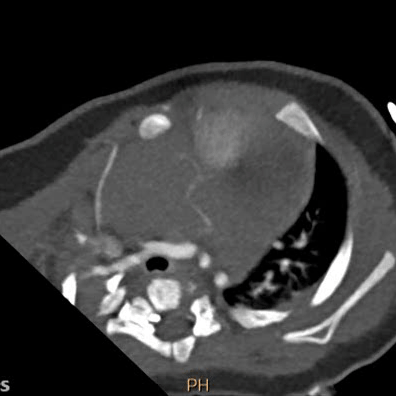

Выполняется трансторакольное ЭХОКГ исследование, которое позволяет заподозрить локализацию и размер опухоли, ее соотношение с другими анатомическими структурами сердца.